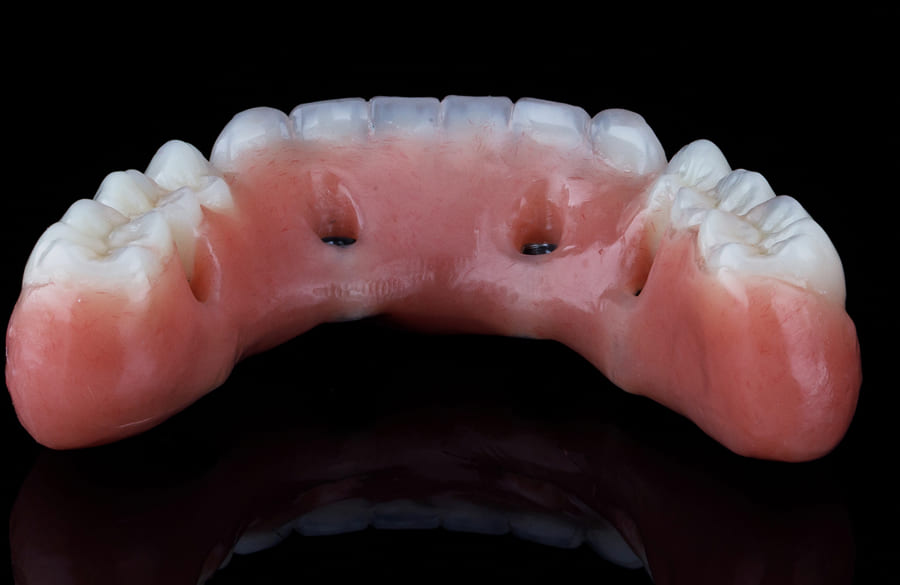

A prótese protocolo é uma estrutura fixa instalada sobre implantes dentários, indicada para pacientes que perderam todos os dentes superiores, inferiores ou ambos. Diferente das próteses móveis, ela fica fixada, o que promove estabilidade.

Esse modelo apresenta uma base metálica resistente que se adapta à arcada, permitindo função mastigatória igual aos dentes naturais. Por isso, é considerada uma “dentadura fixa” que renova o sorriso.

Enquanto a dentadura móvel se apoia apenas na gengiva, a dentadura fixa sobre implantes ganha estabilidade porque é fixada nos próprios implantes que, por sua vez, são integrados diretamente ao osso. Com isso, a prótese protocolo não machuca a gengiva, não cai ao falar ou mastigar e não exige uso de cola ou adesivos.

A manutenção da prótese é simples, mas precisa ser constante para preservar o sorriso. A higiene deve ser feita como em dentes naturais, com escova e fio dental.